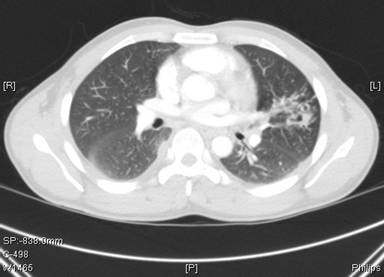

Fig 2: Chest computed tomography at presentation (4 months following initiation of antituberculous therapy)